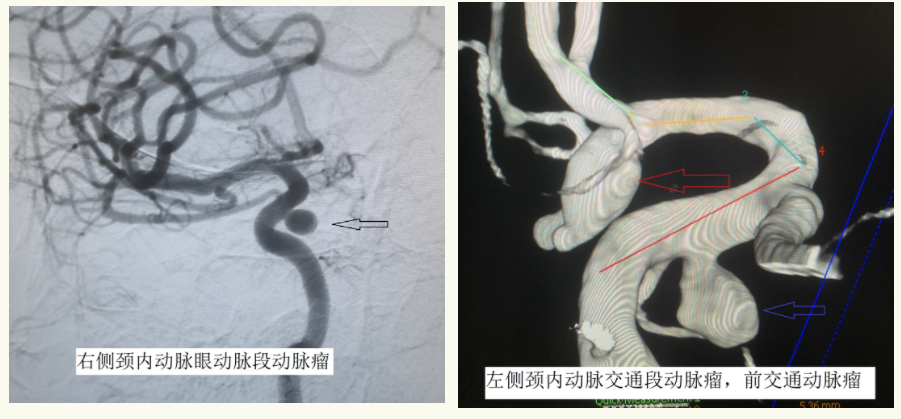

神经外科二组主任王宝庆,副主任医师郭知伟、住院医师王尧在病人病情趋于稳定的情况下迅速为患者做了脑血管造影,明确诊断,找出病因。DSA检查结果显示:颅内多发动脉瘤(右侧颈内动脉眼动脉段动脉瘤,左侧颈内动脉交通段动脉瘤,前交通动脉瘤。其中前交通动脉瘤形态不规则,呈现分叶状有小埠,且与头部CT显示血肿位置一致。前交通动脉瘤破裂出血是本次发病的罪魁祸首。)